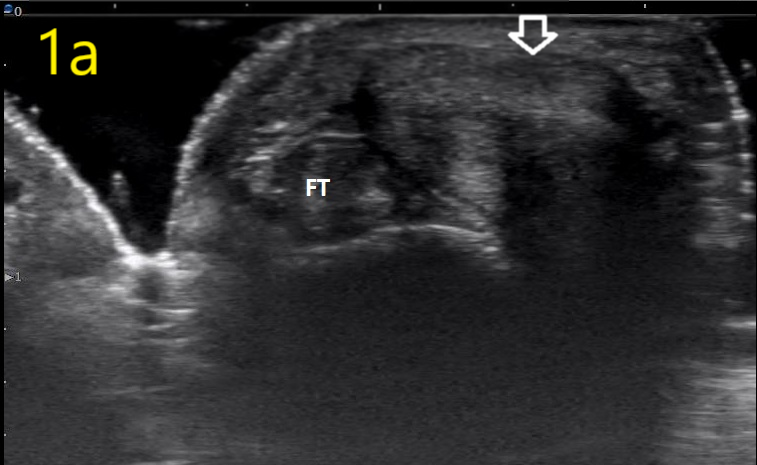

Image 1a

Ultrasound in Orthopedic Practice